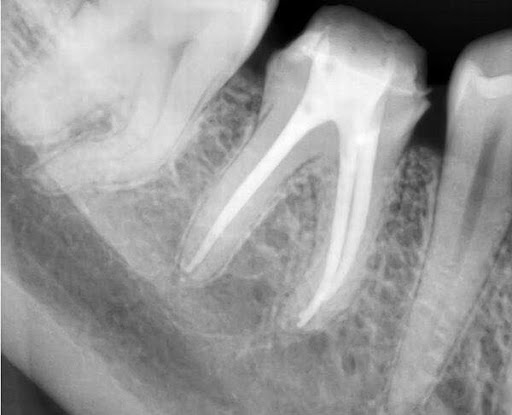

Nếu phát hiện hay nghi ngờ có răng cần phải điều trị tuỷ, bác sĩ sẽ chỉ định chụp phim thêm tại vùng răng đó. Mục đích để đánh giá chính xác hơn mức độ tổn thương và độ khó của răng cần chữa tuỷ.

Để đảm bảo cho toàn bộ hệ thống ống tuỷ được làm sạch. Cần phải chụp các phim đo chiều dài chân răng hay sử dụng máy định vị chóp. Theo đó bác sĩ sẽ phải làm sạch, tạo hình tới đúng chiều dài chân răng. Đảm bảo không còn mô tuỷ hay vi khuẩn còn sót lại trong ống tuỷ.

Quá trình trám bít ống tuỷ là sử dụng vật liệu trám bít ống tuỷ kết hợp với các dụng cụ để bít kín toàn bộ hệ thống ống tuỷ. Mục đích ngăn chặn sự xâm nhập của vi khuẩn. Sau trám bít cần chụp phim kiểm tra lại việc trám bít đã tốt hay chưa?